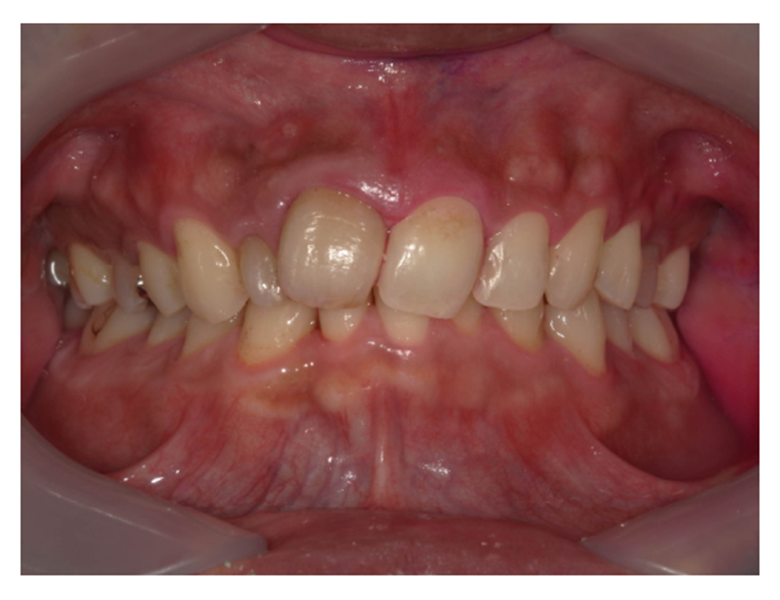

治療前

| カウンセリング・診断結果 | 口腔内を拝見したところオレンジ色に変色したプラークや歯石が岩のようになって下の前歯の裏側に沈着しているのを確認しました。 今以上歯周病が進行しないためにも、患者様にクリーニングを受けて頂くよう説明しました。 |

| 行った治療内容 | 口腔内の状況を把握する為 ・口腔内全体のレントゲン撮影 ・口腔内写真 ・歯周検査 ・染めだし、歯磨き指導 プラークや歯石を取り除く ・スケーリング ・歯面研磨 を行いました。 |

| 術後の経過・現在の様子 | 以前に比べて口腔内に対しての意識が変わりブラッシング方法の改善により、プラークの付着量を減らすプラークコントロールができるようになり、歯ぐきの炎症や出血が軽減されつつあります。 しかし、まだ歯ぐきの腫れや出血が残っているところもあるため、セルフケアと定期的な検診・クリーニングで歯周病を予防し、引き続き経過を観察しています。 |